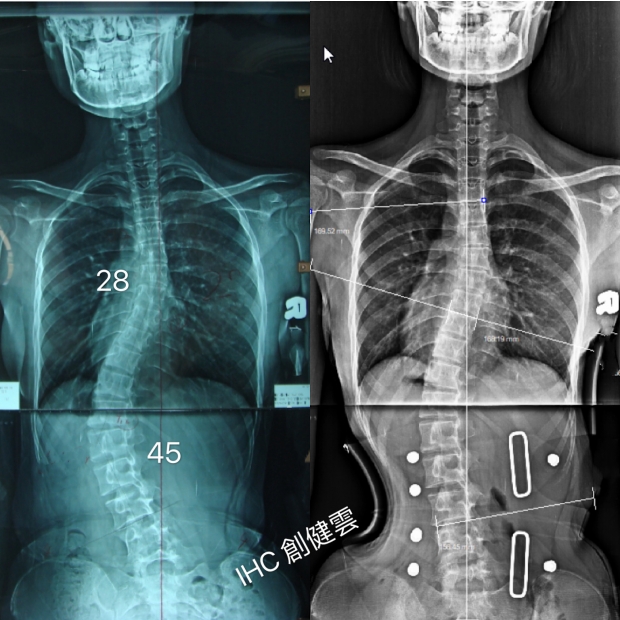

18歲脊椎側彎女孩

胸彎28度,腰彎45度